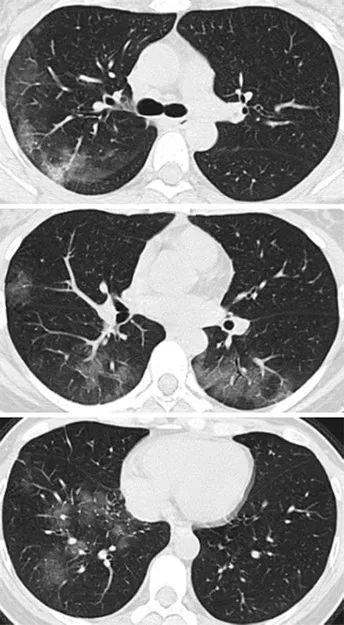

下面例举2个新冠病毒导致的肺炎病例,

病例资料来自《Radiology》杂志。

病例1,33岁女性,在武汉工作,

今年1月份回到兰州后

第二天开始发热,咳嗽,

5天后,她去医院检查,

她咽喉部分泌物中发现新冠病毒核酸,

肺部CT扫描(见下图A)

两侧肺上叶肺段呈斑片状毛玻璃样显影。

医生给她用了很多药物,

甚至用上了干扰素,

3天后,再次CT检查发现,

两肺的毛玻璃显影更大了(图片B),

显示治疗效果不好,病情加重。

病例2,41岁女性,去了一趟武汉,

回来后,开始发热咳嗽,

4天后,她感觉呼吸困难,

去医院X线胸部拍片,检验血液,

都没有发现有啥异常。

但是CT扫描发现

两侧肺周边出现多处斑片状毛玻璃样显影。